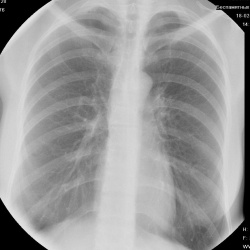

Пациентка 73 лет, доставлена в приёмное отделение с подозрением на пневмонию, t до 39 в течение 3-х дней, слабость, кашель, одышка в покое. После снимка ОГК госпитализирована, сразу выполнена...